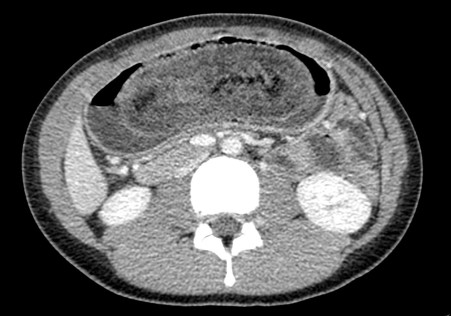

Lipoma intestinal: frecuente como punto guía o cabeza de invaginación en el instestino delgado. Aquí presentamos un caso de lipoma intraluminal en el colon, que producia obstrucción y cambios inflamatorios en el colon ascendente.